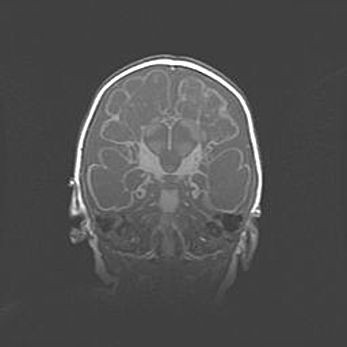

Наружная гидроцефалия с возможной атрофией височных областей.

Возраст: 28 дней

Вес: 3670 г

Пол: мужской

Окружность головы: 38 см

Срок гестации: 40 недель

Гидроцефалия головного мозга у новорожденных – это заболевание, которое характеризуется скоплением избыточного количества спинномозговой жидкости в желудочковой системе головного мозга в результате затруднения её перемещения от места выработки к месту поглощения в кровеносную систему или вследствие нарушения абсорбции. При открытой наружной форме гидроцефалии у новорожденных расширяются и переполняются субарахноидные пространства.

При нормотензивных  формах,  которые,  как  правило,  являются  следствием  перенесенных ишемических  повреждений  паренхимы  мозга,  возможно  сочетание микроцефалии  с нормотензивной гидроцефалией. В основе данных изменений лежит атрофия больших полушарий с преимущественной  локализацией  в  лобно-височных  областях.